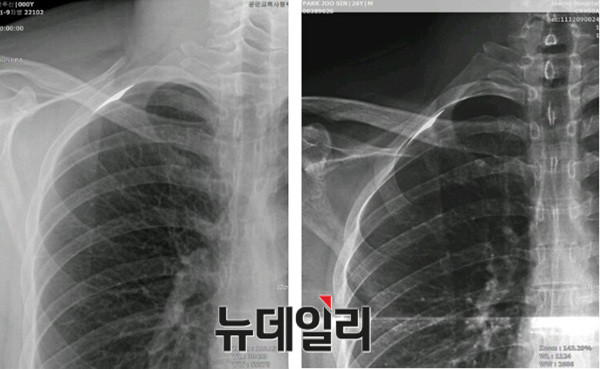

- ▲ (왼쪽부터) 박주신씨 명의 공군-자생-비자발급 엑스레이. 피고인들은 이 중 자생병원 엑스레이를 대리인의 것으로 보고 있다. ⓒ뉴데일리 정상윤 기자

박주신씨의 신체를 촬영한 것으로 알려진 엑스레이는 모두 3장이 있다. 이 중, ‘공군훈련소 입소 당시 엑스레이’(촬영일자 2011년 8월 30일, 이하 공군 엑스레이)와, 주신씨가 ‘비자발급을 위해 촬영한 세브란스병원 엑스레이’(촬영일자 2014년 7월 31일, 이하 비자발급용 엑스레이)는 피고인들도 박주신씨 본인의 것으로 보고 있다.

반면 피고인들은, 박주신씨가 병역처분 변경을 위해 병무청에 제출한 자생병원 엑스레이(촬영일자 2011년 12월 9일)는, 주신씨가 아닌 대리신검자의 것으로 의심하고 있다.